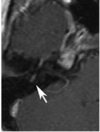

A 23-year-old woman is evaluated because of Bell palsy. An MR image with contrast of the facial nerve is shown. The arrow corresponds to which of the following segments of the facial nerve?

A. Labyrinthine segment

B. Meatal (canalicular) segment

C. Tympanic segment

D. Mastoid segment

E. Extratemporal segment

A

Correct Answer: Mastoid segment